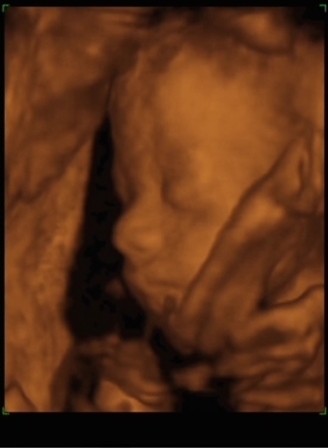

Panka 22 hét 4 naposan. 4D Genesisben készült.